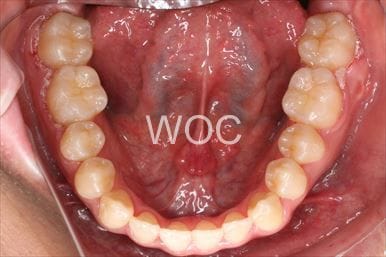

治療前1

治療前2

治療前3

治療前4

治療前5

- 年齢:20歳女性

- 主訴:出っ歯が気になる

- 基本矯正料金:120万円

- 治療期間:1年7ヶ月

- 抜歯部位:上顎両側第一小臼歯